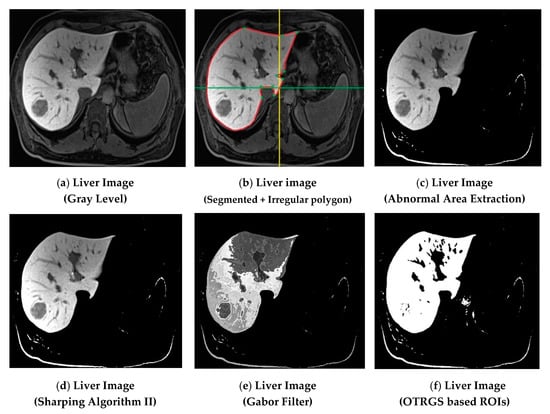

Now, let us discuss the proposed methodology in detail. The first step consisted of a collection of image datasets with two categories of liver cancer. These two categories are (i) benign liver cancer, which includes a further three subcategories (hepatocellular adenoma, hemangioma, and cyst), and (ii) malignant liver cancer, which includes three subcategories (hepatocellular carcinoma, metastasis, and hepatoblastoma). In this step, for each type, 100 patients were selected to examine their liver cancer using a CT scan, and 100 patients were examined using MR images of a size of 512 × 512, and a dataset of 1200 (100 × 6 × 2) fused (MR and CT) images of a liver cancer patients was acquired from the radiology department of Bahawal Victoria Hospital Bahawalpur, Pakistan [20]. The second step is image preprocessing. In this step, firstly, digital MR and CT images were converted into a gray-level eight-bit image format. Secondly, noise removal was performed using “Gabor filters”. Thirdly, we enhanced the images using “Sharping Algorithm II” to sharpen the edges of the image, then a data cleaning was done for liver cancer image dataset standardization. The third step was segmentation, which helped to remove the extra object, nominate the exact position, and refine the texture of the lesion. There are several automated and semiautomated methods for extracting ROI. Automated ROI extraction is generally based on the idea of image segmentation, but there is no single technique for ideal segmentation. On the other hand, there are semiautomated techniques based on expert opinion, but human-based extraction has some limitations. To solve this problem, Otsu thresholding-based region growing segmentation (OTRGS) was employed on the liver cancer fused image dataset. The segmentation process is shown in Figure 3. The fourth step was first-order and second-order hybrid-feature extraction. In this step, four types of features, namely, “Co-Occurrence Matrix Feature”, “Wavelet Feature”, “Run-Length Matrix feature”, and “Histogram Feature”, were extracted from the standardized liver cancer (MR and CT) image dataset. The fifth step was the formation of a fused hybrid-feature dataset using the data fusion technique. The sixth step was fused hybrid-feature optimization. In this step, we selected the best 10 optimized fused hybrid features of the extracted feature dataset using probability of error, plus the average correlation feature selection technique. The last step was classification, where four ML classifiers named multilayer perceptron (MLP), support vector machine (SVM), random forest (RF), and J48 were employed (using cross-validation 10) on a selected optimized fused hybrid-feature dataset.

Figure 3. Otsu thresholding-based region growing segmentation (OTRGS) framework for liver cancer.